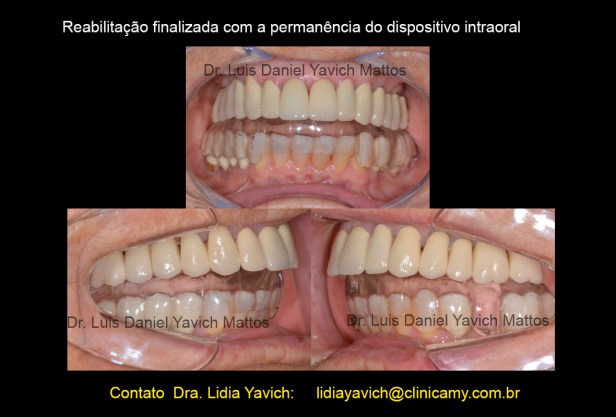

Nesta vista sem o dispositivo intraoral, com as coroas metalo-cerâmicas já cimentadas, se mostra o setor incisivo inferior com desgastes a serem reabilitados com resinas.

Neste caso o planejamento inicial foi manter um dispositivo intraoral após a reabilitação, já que a perda dimensional era muito grande.

Fotografias intraorais pre e pós tratamento.

Fotografias intraorais pre e pós tratamento.

Fiquei com um dispositivo intraoral pequeno que vai ser trocado em pouco tempo por um dispositivo intra-oral estético.

ESTÉTICAMENTE MELHOROU A MINHA AUTOESTIMA, mesmo que isso não TENHA SIDO o motivo da procura. O motivo era aliviar as minhas dores, agora SEM DOR, TAMBÉM A ESTÉTICA É IMPORTANTE.